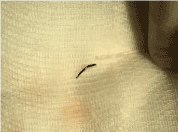

Trans-radial coronary angiogram revealed tortuous and aneurysmal dilatation (ectatic vessels) of all three major coronary arteries (Figure 3a, 3b) with huge thrombus in the proximal segment of left circumflex (LCx) artery, the culprit lesion was identified. Left coronary system was engaged with XB 3.0 6-French guiding catheter through right radial access with 6F sheath. The lesion was crossed by Run through NS floppy (Terumo) hydrophilic 0.014 inches wire. Among different strategies to deal with huge thrombus burden such as Plain Old Balloon Angioplasty (POBA), thrombus aspiration and intracoronary glycoprotein IIb/IIIa inhibitor, we proceeded with thrombus aspiration. Thrombuster II (Kaneka Corporation) thrombus aspiration catheter introduced into the target vessel and suctioning performed. Blood clots aspirated as shown (Figure 4). After few aspirations, failed to do further suctioning and planned to flush as the catheter may get blocked from aspirated thrombus. Some degree of resistance was felt while removing the catheter from the vessel. The thrombus aspiration catheter finally came out with slight pulling force but noted that the tip was missing (Figure 5). Angiographically, the tip of Thrombuster II catheter seen attached to the guidewire (Figure 6). The guidewire can move freely along the mid and distal LCx but failed to withdrawal at the proximal LCx area.

Figure 4. Aspirated thrombus with Thrombuster II